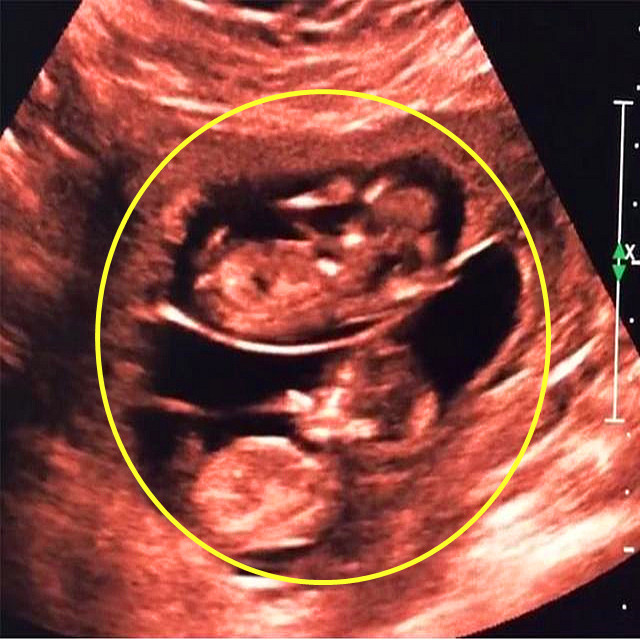

盛济妇产科医生杜帝瞧瞧,这两个孩子多健康啊!

盛济妇产科医生杜帝

作者百度,没有别的了,将就看吧!